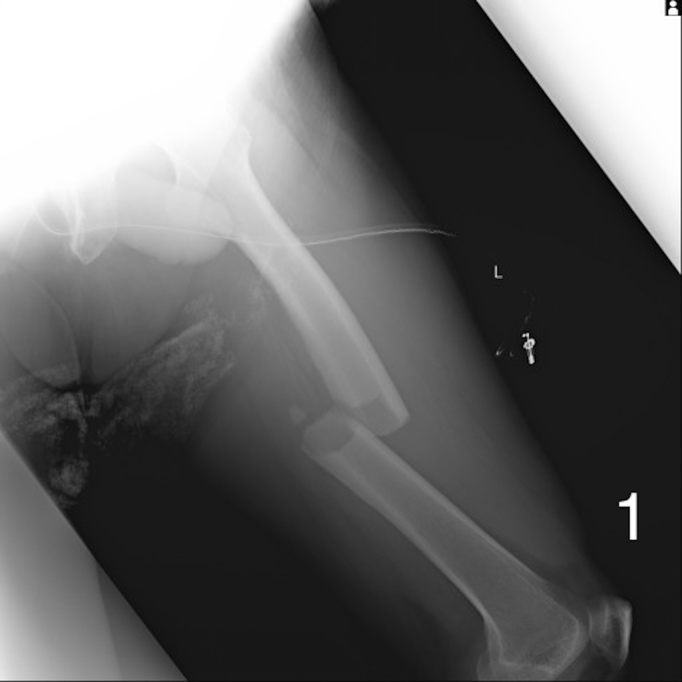

Abstract Image